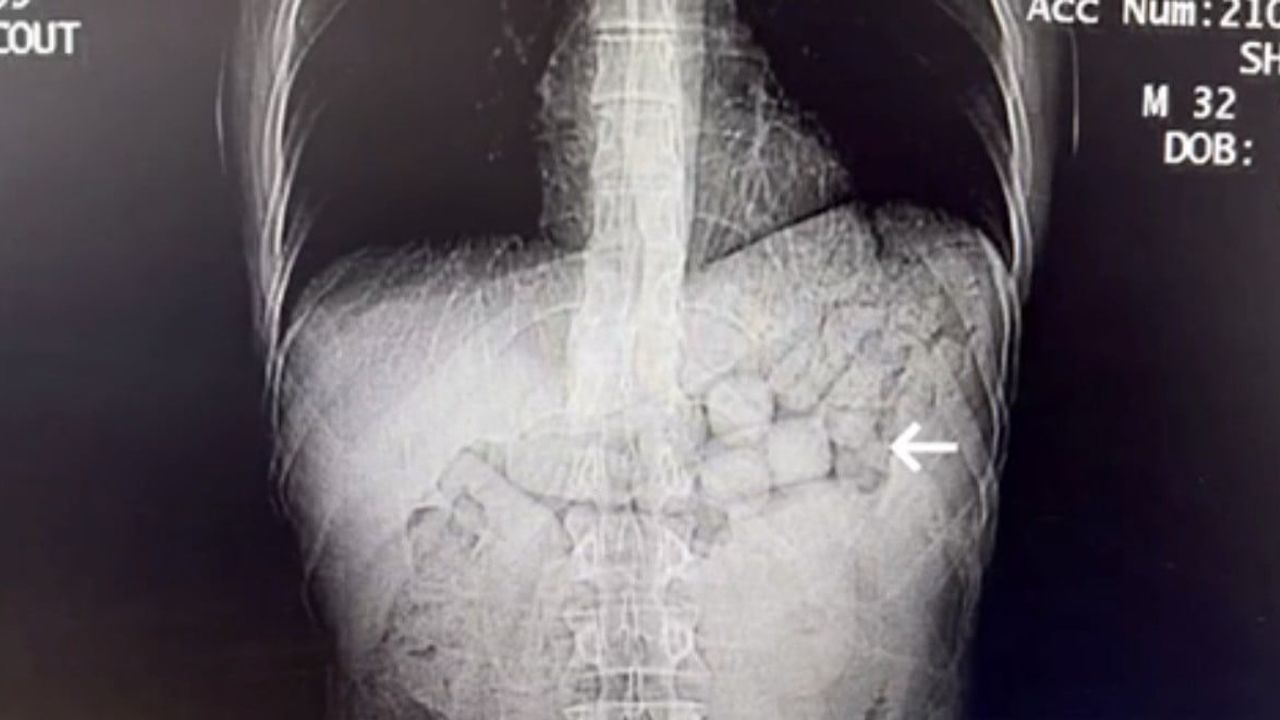

Çekilen tomografi görüntülerinde şüphelilerin mide ve bağırsak bölümlerinde yabancı cisimlere rastlandı.

Yaklaşık 3 gün süren tıbbi kontroller sonucunda şahıslardan 91 kapsül içinde toplam 807,15 gram Metamfetamin ele geçirildi. Şüpheliler gözaltına alındı ve emniyetteki işlemlerinin ardından sevk edildikleri adli makamlarca tutuklandı.